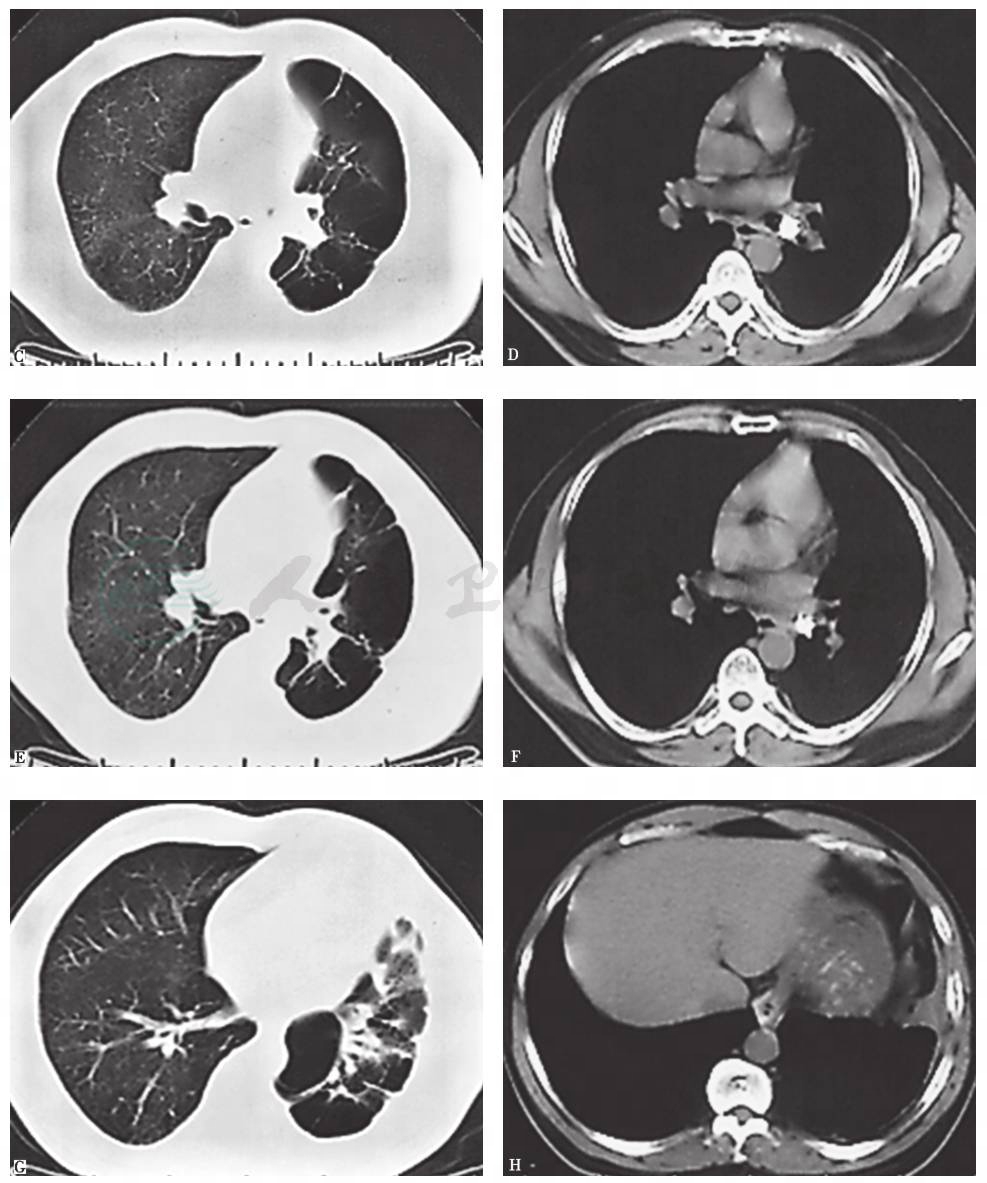

经规律抗感染治疗10天后,患者体温恢复正常,肺灌注显像证实患者左肺无功能,肺功能检查明确患者可耐受一侧全肺切除术,遂对患者行外科手术,切除左肺及左主支气管肿物并做病理检查 (图15、图16)。

图16 左肺标本病理表现

肺组织正常结构基本消失,以纤维囊壁组织为主,肺组织支气管周灶状淋巴细胞浸润,结合临床表现,考虑符合肺大疱表现 (A.HE染色,100×);左主支气管肿物为以软骨为主要成分的肺错构瘤(B.HE染色,4×;C.HE染色,100×)

引自:主编:.呼吸系统疑难病例诊疗辨析.第1版.ISBN:978-7-117-26415-0

最后诊断:左主支气管错构瘤,肺大疱合并感染。